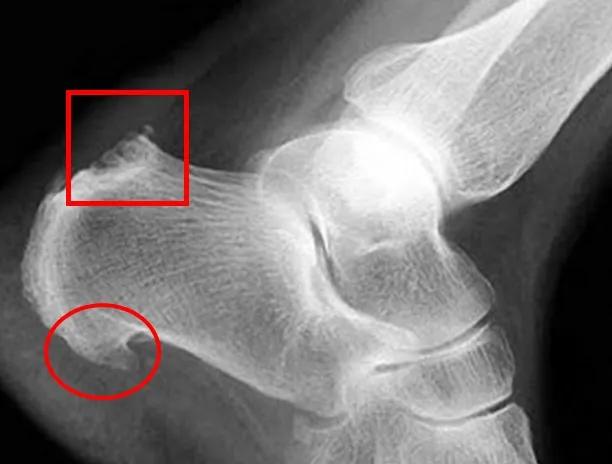

3.跟骨骨刺

多见于老年患者,当有足跟痛时,经过拍摄X光片,可以发现跟骨结节处有大小不一的骨刺形成(图4,圈内)。隆起的骨刺,也可以导致局部组织受到激惹、摩擦、劳损,产生无菌性炎症,其足跟疼痛的程度与局部炎症反应的轻重有关,而与骨刺大小无直接关系。

药物或微创手术可以改善症状、解除疼痛。

▲ 图4.足跟部骨刺(圈内),跟骨骨突肥大(框内)

5.跟骨骨突炎

又称Hugland畸形,表现为跟骨后方骨突的肥大(图4,框内),也可以表现为类似胫骨结节骨骺炎的情况,是在发育过程中,未愈合的骨骺受肌腱牵拉引起的症状,疼痛在跟腱附着点周围,负重行走可加重。通常可以使用药物,休息,穿坡鞋治疗,一般对症处理有效,巨大的跟骨骨突炎或保守治疗无效的患者,需要手术治疗。